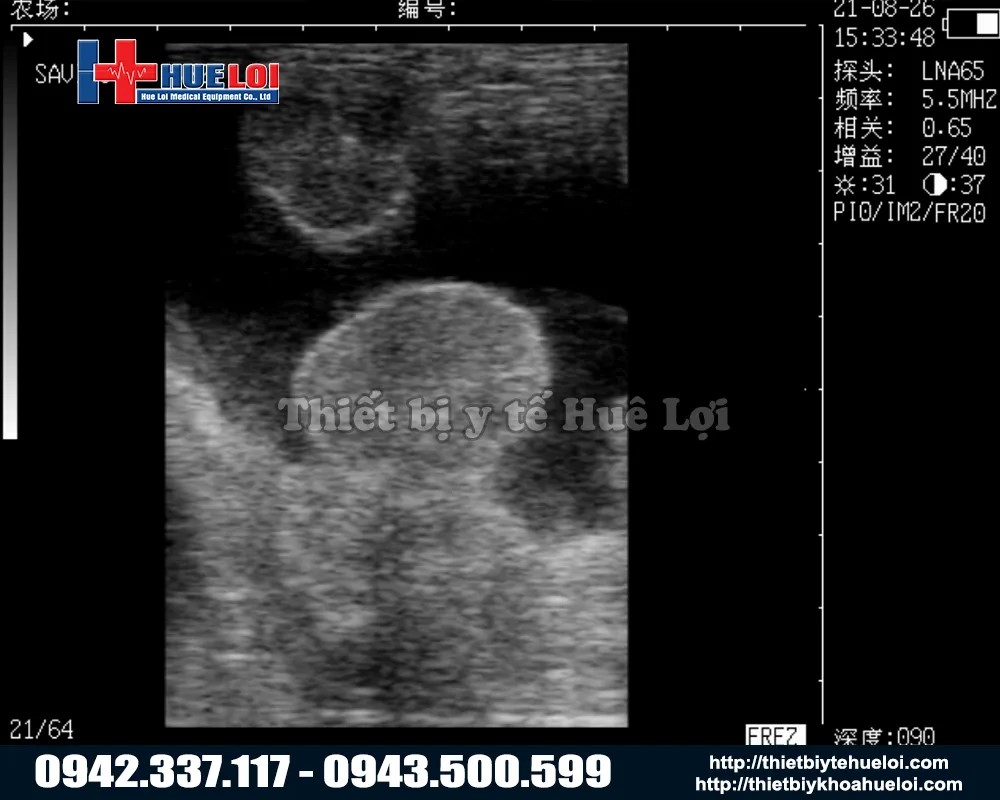

- Công Nghệ Hình Ảnh "Mimage" Vượt Trội

Dù là máy cầm tay nhỏ gọn, M3V được trang bị nền tảng siêu âm y tế với công nghệ hình ảnh "Mimage", mang lại chất lượng hình ảnh chẩn đoán sắc nét và rõ ràng đáng kinh ngạc. Với màn hình LCD 7 inch lớn so với các dòng cầm tay (thường chỉ 5-5.5 inch). Tỷ lệ 16:9 giúp việc quan sát các chi tiết nhỏ trở nên dễ dàng hơn bao giờ hết.